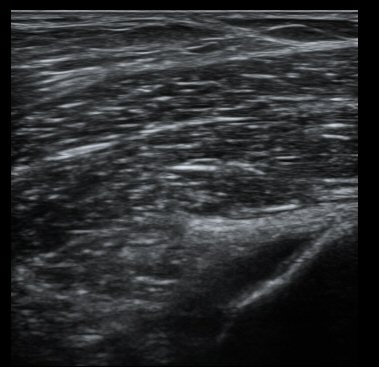

´ëÅð°ñ ¿ÜÃø°ú ¾ÕÂÊ Á¾´Ü¸é°Ë»ç¿¡¼­ ¾à°£ÀÇ ¼ö¾×Àú·ù°¡ °üÂûµÊ(±×¸² 1, 2).